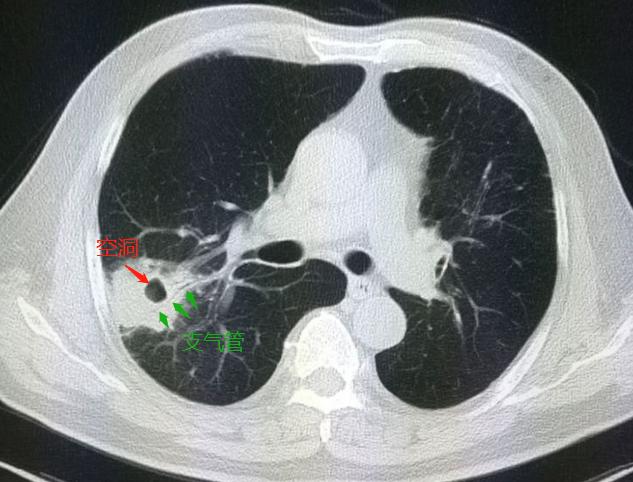

肿块整体缩小了一圈,而且里面出现了一个空洞(红箭头),空洞壁似乎还能看到支气管的影子。

为了看得更清楚,我们把图像再放大一点:

空洞壁果然看到一支平行走向的支气管影,同时我们可以看到,肿块周围的云雾状磨玻璃影已经完全吸收了(说明抗生素治疗很有效)。

这就充分说明了这个肿块不是肺癌,而是一种感染性病变——肺脓肿。